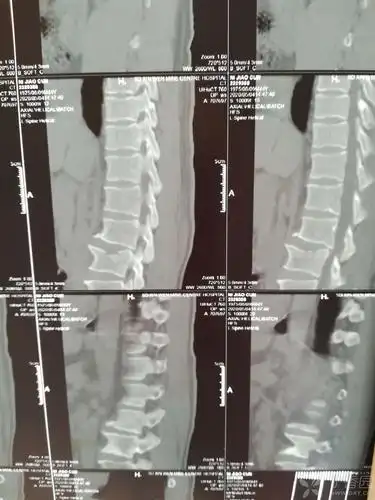

患者外伤入院,术前x线片示腰5椎体压缩性骨折,腰4椎体滑脱,腰椎不完全

年轻患者腰椎压缩性骨折,钉棒固定,减压复位 - 好大夫在线